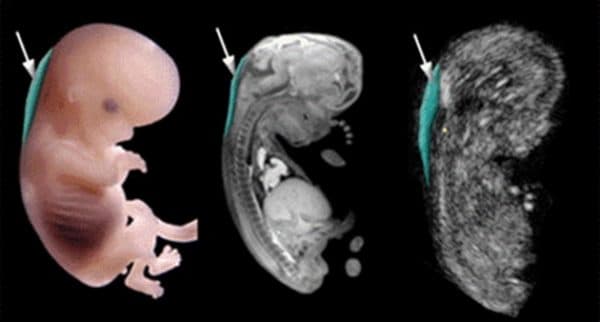

2. Độ mờ da gáy bao nhiêu là tốt?

Chỉ số đo độ mờ da gáy dưới 2,5mm được xem là an toàn.

Trước hết để biết độ mờ da gáy bao nhiêu là tốt cần chắc chắn chỉ số này được lấy trong khoảng từ tuần thứ 11 đến tuần thứ 13. Trong khoảng này, độ mờ da gáy thường tỉ lệ thuận với tuổi thai, tức là thai nhi càng lớn độ mờ da gáy càng tăng. Ví dụ thai nhi 11 tuần tuổi độ mờ da gáy bình thường là 2mm nhưng tới 13 tuần 6 ngày kết quả 2,8mm vẫn được xem là bình thường. Do đó độ mờ da gáy bao nhiêu là tốt cần căn cứ vào thời điểm thực hiện.

Độ mờ da gáy từ 3mm trở lên cho biết nguy cơ bị dị tật down là 70% và cần thực hiện thêm các xét nghiệm chuyên sâu khác. Chỉ số dưới 2,5mm cho biết độ mờ da gáy ở mức an toàn.